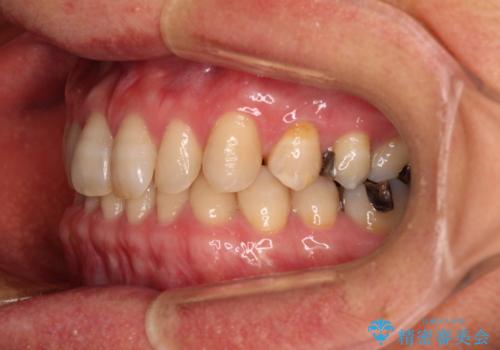

- 前歯のデコボコと隙間の空いた歯列を気にして来院された患者様です。

下顎前歯が隠れるほどのディープバイトにより、強い咬合力と突き上げで上顎歯列に隙間が空いている状態でした。

手前に傾斜している奥歯をワイヤー装置で立ち上がらせ、咬み合わせの高さを挙上することで突き上げを解消し、空隙歯列を改善していくこととしました。

ディープバイトが改善され、睡眠時の食いしばりも緩和され、顎への負担が軽減されました。